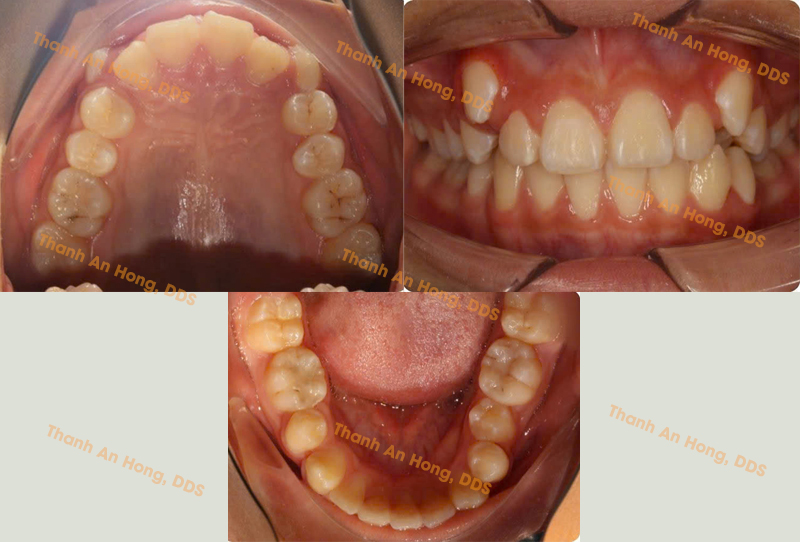

HÌNH ẢNH THỰC TẾ

Sắp đều răng trong độ tuổi tăng trưởng với mắc cài